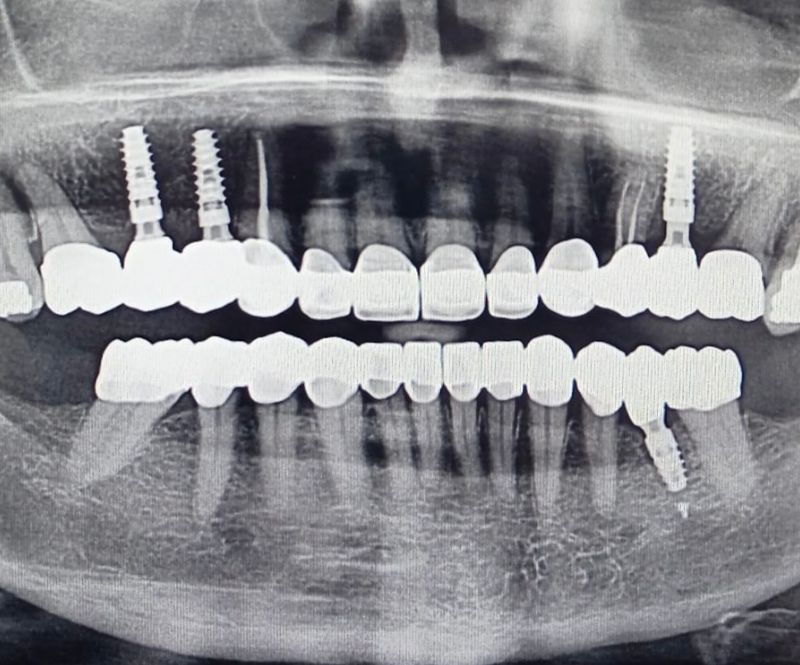

En Oral Park transformamos sonrisas con materiales de máxima calidad. En este caso, combinamos zirconio monolítico en el sector posterior y zirconio-cerámica en el anterior, logrando una estética natural y resistencia óptima.